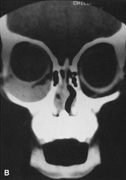

Valuable information about the nature and extent of an orbital pathologic process is provided by imaging studies such as computed tomography (CT) scan, magnetic resonance imaging (MRI), and orbital echography. Better spatial resolution, ready accessibility, and lower cost make CT the preferred choice for orbital imaging in most cases. Orbital fat provides a natural contrast between most adjacent orbital structures on CT scanning, and orbital bones are visualized well. Computed tomography is essential for evaluation of the orbital bones because they cannot be imaged with MRI. Direct coronal or sagittal images are important to identify the relationship of a lesion to the optic nerve so that the surgical approach can be planned to avoid traversing the optic nerve (Fig. 1).

Fig. 1. A. Axial CT scan demonstrating a large, well-encapsulated lesion in the orbital apex. Coronal (B) and sagittal (C) scans demonstrate that the mass lies inferior and medial to the optic nerve within the intraconal space. This information is useful in planning the surgical approach to the mass, which should avoid traversing the optic nerve.